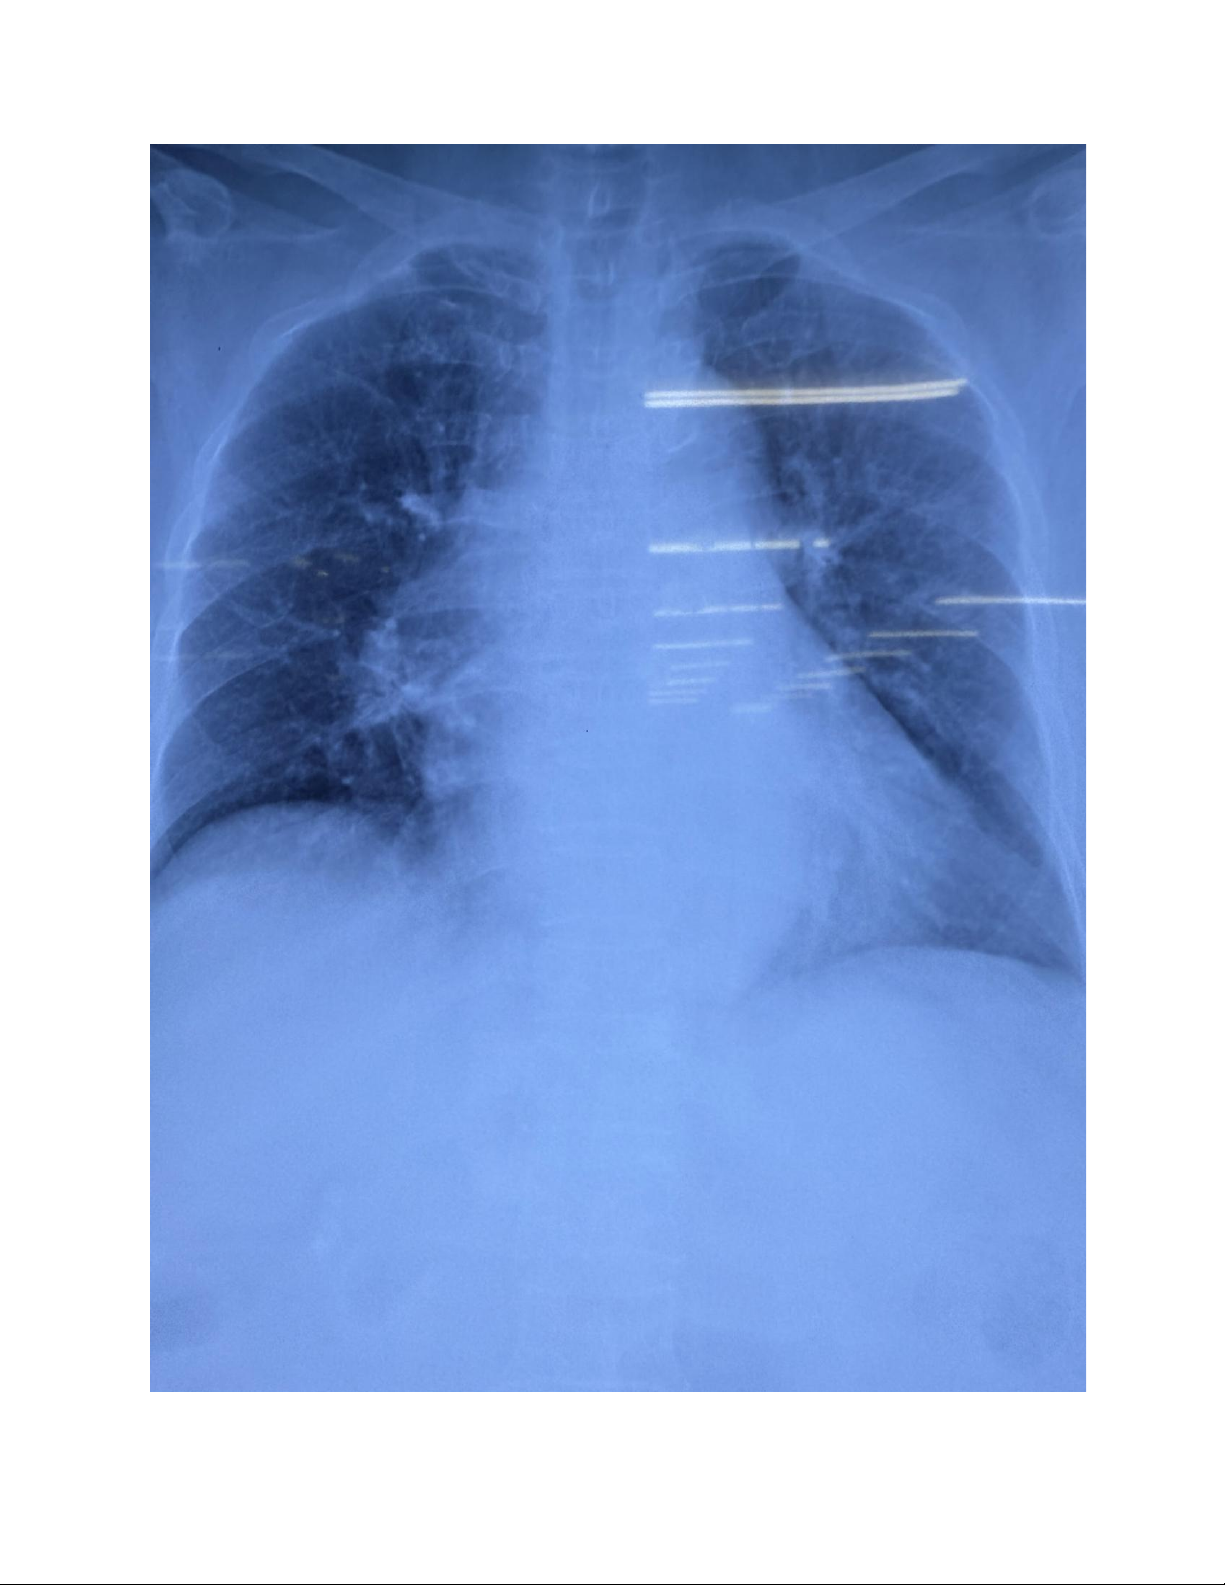

7. X-quang ngực thẳng Ngày 20/09/2025: lOMoAR cPSD| 47206521 lOMoAR cPSD| 47206521 ● Hành chính:

- Tên bệnh nhân: BÙI THỊ C. - Tuổi: 80.

- Ngày tháng chụp: ngày 20/09/2025. ● Kỹ thuật:

- Tư thế chụp: AP (2 xương bả vai trong phế trường, không bóng hơi dạ dày, tuần hoàn

phân bố đều trên dưới).

- Chất lượng phim tốt, cường độ tia trung bình, tư thế nằm, bệnh nhân hít đủ sâu).

● Đọc X-Quang: khảo sát theo ABCDE. . Airway: - Khí quản không lệch.

- Gốc Carina bình thường. . Breathing:

- Khí quản thông thoáng, không hẹp hay tắc nghẽn.

- Tổn thương dạng đông đặc, gần rốn phổi hai bên. Hình ảnh thâm nhiễm dạng lưới/ nốt tập

trung rải rác 2 phế trường.

- Hình ảnh giãn phế quản hai bên.

. Cardiac: quan sát được góc sườn hoành, không có bóng hơi dạ dày.

- Kích thước và hình dạng tim:

+ Chỉ số bóng tim/lồng ngực > 0.6 => Bóng tim lớn. . Diaphragm:

- Chưa ghi nhận bất thường. . Else:

- Khoang liên sườn giãn rộng.

KẾT LUẬN: Tổn thương dạng đông đặc gần rốn phổi 2 bên kèm thâm nhiễm dạng lưới/nốt rải